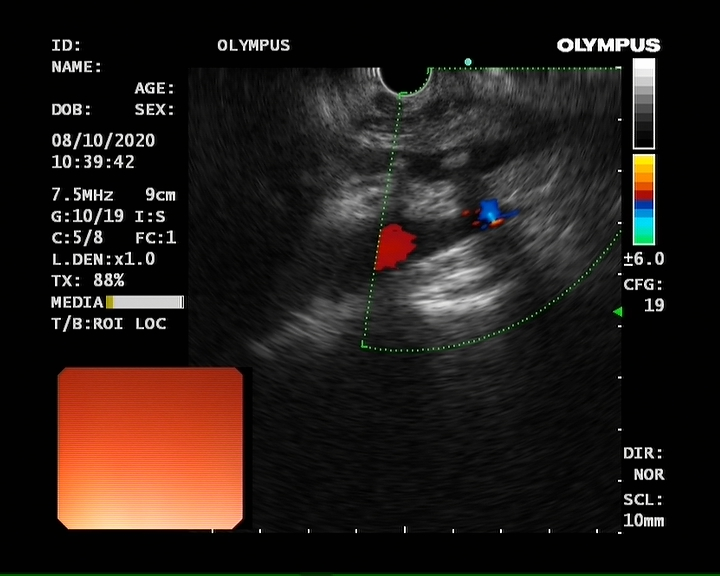

⑦超声胃镜

EUS是将微型高频超声探头安置在内镜前端,在内镜直视观察腔内形态的同时,又可进行实时超声扫描近距离探查,使靶器官的结构与图像更为清楚,为临床治疗方案的选择提供了有力的支持。我院消化内镜于2004年在四川省率先开展EUS新技术,目前拥有国内最新—代的EUS系统,它集超声内镜主机、高频小探头、三维超声探头、环扫内镜超声等 先进设备为—体。我院EUS诊疗组,现有教授1名、副教授2名,每年完成近千例消化道EUS诊疗,EUS诊疗技术达到省内先进水平。

为什么需要EUS

普通内镜检查只能发现消化道表面的病灶,通过EUS显示消化管壁层次结构及周围脏器病变,能更准确判断胃肠隆起病变的 性质、来源、肿瘤的浸润深度,还能取活检,指导确定治疗方案及判断疗效。

EUS适应症

1、消化道肿瘤的诊断,术前分期、术后随访

2、判断粘膜下肿瘤的起源与性质

3、胰腺与胆道疾病的诊断与鉴别

4、食管胃底静脉曲张的诊断与疗效判断

5、溃疡性病变良恶性的判断

6、各种需要EUS介入治疗的疾病

EUS诊疗新技术

1、超声内镜引导下胰腺病灶细针穿刺抽吸术(EUS-FNA)

2、EUS引导下放射性粒子植入术

3、EUS引导下射频治疗中晚期胰腺癌;

4、EUS引导下腹腔神经节阻滞术

5、EUS 引导下胰腺囊肿、脓肿穿刺置管引流术